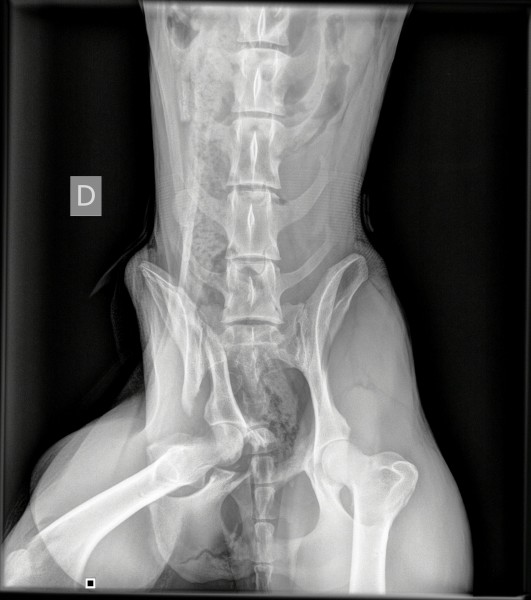

L’intervention sur le bassin de Mel a été une réussite, le chirurgien a atteint ses objectifs :

redresser le bassin, réaligner les abouts osseux fracturés puis stabiliser au moyen d’une

plaque avec vis qu’elle gardera à vie si elle le supporte bien.

Une radiographie de contrôle aura lieu dans 7-8 semaines ; durant ce temps, pas de course,

pas de saut et des sorties en laisse puis sera mis en place un programme de physiothérapie ;

Regardez sur les photos jointes, son bassin avant et après….

AVANT

APRES